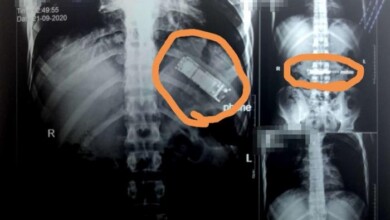

يعيش بهاتف في معدته منذ 7 أشهر.. ويكشف سر ابتلاعه

قد يبتلع البعض أشياء صلبة عن طريق الخطأ أحياناً، لكن هل يمكن أن يبتلع أحد هاتفاً محمولاً ويستقر في معدته…